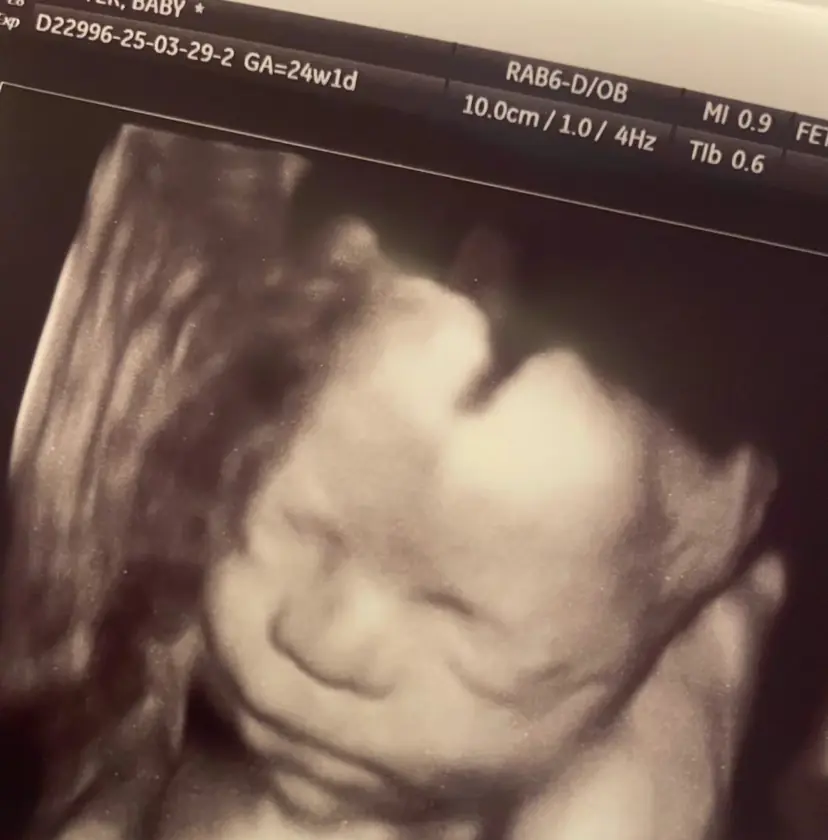

Amanda Foster, uma mãe cristã dos Estados Unidos, chamou a atenção nas redes sociais após compartilhar um ultrassom que, segundo ela, mostra uma mão misteriosa sobre a cabeça do bebê. A imagem, feita durante um exame de rotina, gerou reações e interpretações de fé entre os seguidores.

“Fiz uma ecografia ontem, a minha filha mais nova, Bailey, foi a primeira a reparar e me perguntou de quem era a mão, depois o Kyle [meu marido]. Em uma das fotos tem a aparência de uma mão segurando sua cabeça”, relatou Amanda.

Ela contou que costuma orar antes de cada exame. “É a mão de Deus. Não sei como explicar de outra forma”, afirmou em vídeo publicado no TikTok. Na legenda, a mulher relatou a emoção ao ver a imagem que considerou um sinal de proteção.